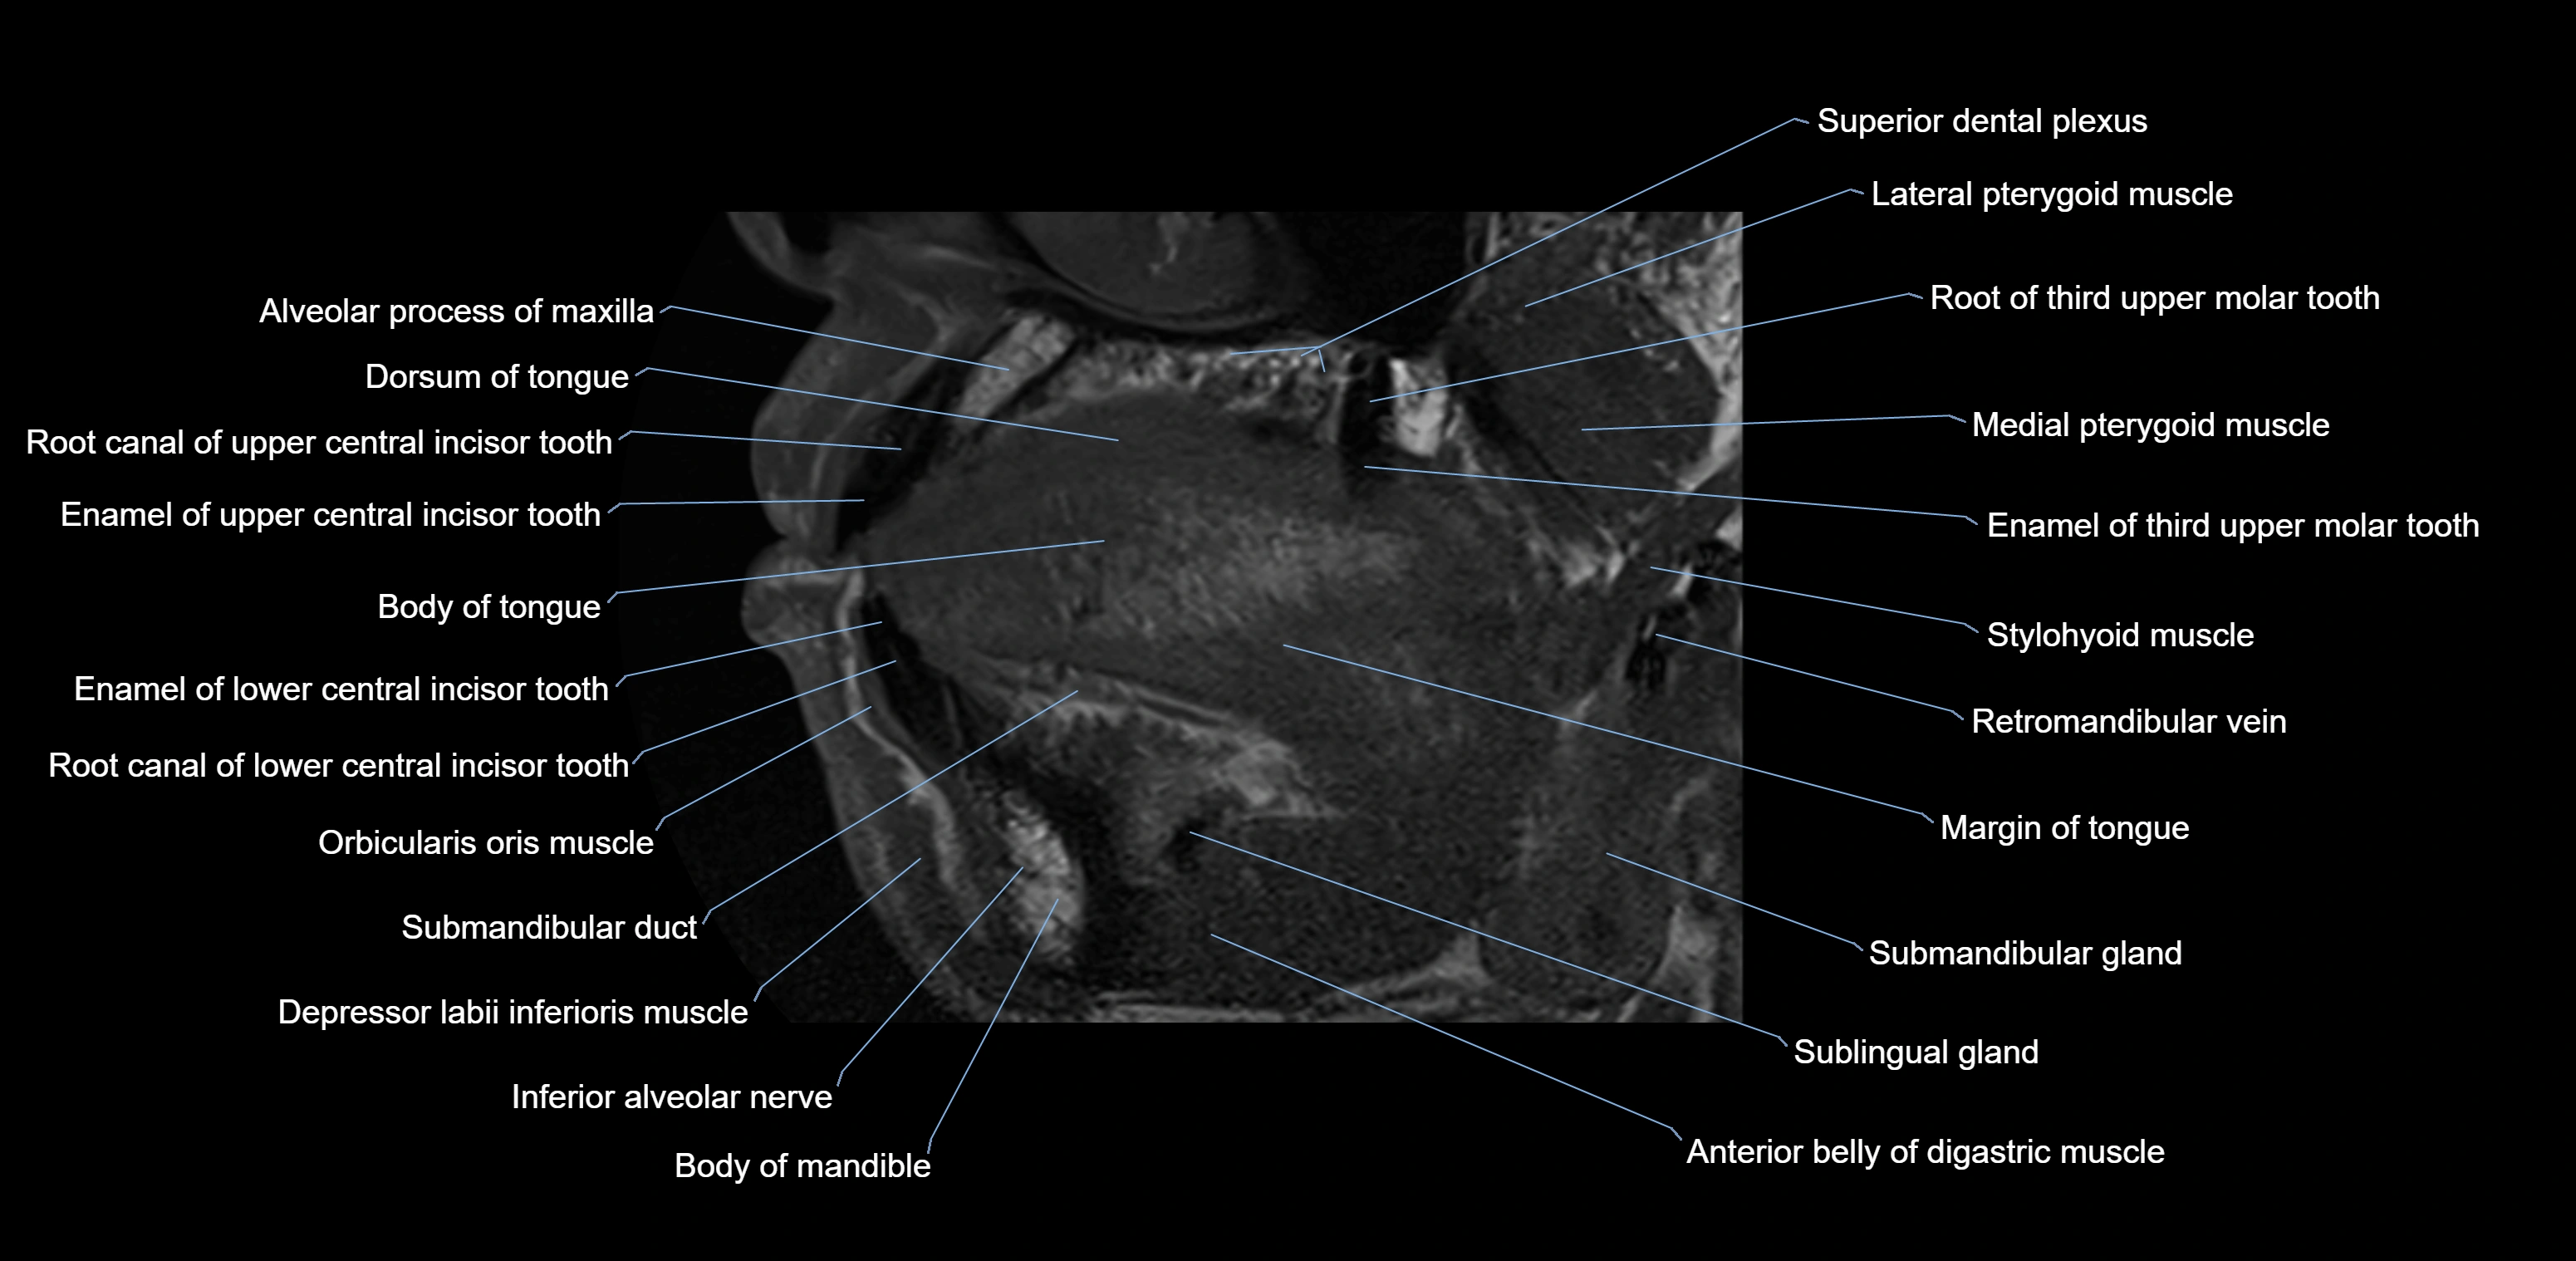

- Anterior belly of digastric muscle

- Body of mandible

- Body of tongue

- Dorsum of tongue

- Inferior alveolar nerve

- Mylohyoid muscle

- Orbicularis oris muscle

- Stylohyoid muscle

- Superior dental plexus